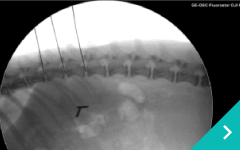

胸腔鏡下

乳び胸(Chylothorax)

心膜切除手術